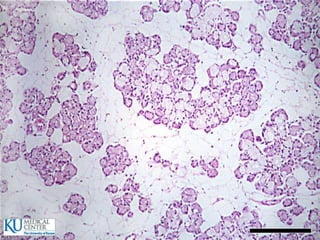

ID: Células cilíndricas Cada célula tiene un borde en cepillo  Borde PAS positivo en relación con el Glucocáliz  El glucocáliz es resistente a los proteolíticos y mucolíticos  Las microvellosidades tienen un centro con filamentos finos de actina que se mezclan con el velo terminal que tiene miosina  Absorben azúcares y aminoácidos por un proceso activo y pasan al espacio extracelular por difusión pasiva

• 65.

 Absorven lípidos:Los lípidos primero son captados por las miscelas intraluminales de sales biliares, que los estabilizan en una emulsión y los transportan al borde estriado donde difunden al interior de la célula como ácidos grasos  Estos ácidos se unen a un componente glucoproteínico (apoproteína) en el retículo de golgi  Las gotitas de quilomicrones de lipoproteína así formados pasan hacia los espacios intercelulares y se dirigen hacia abajo para atravezar la lámina basal y entrar a los vasos linfáticos (quilíferos), de la lámina propia